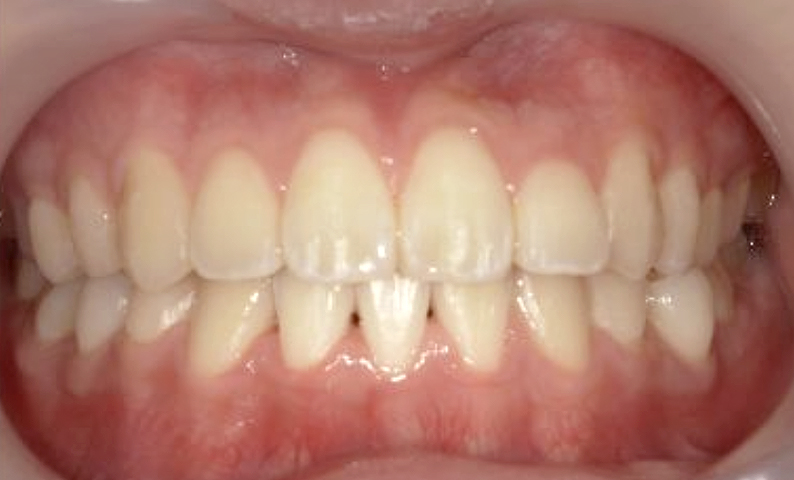

症例_023 上顎だけの部分矯正

治療期間:9ヶ月金額:30万円+税女性前歯のガタガタ上の前歯だけ

| Before | After |

|---|---|

|